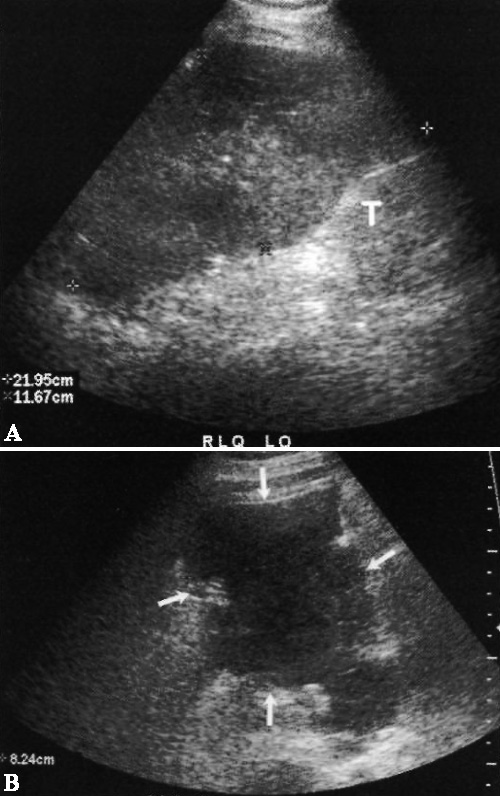

Ультразвуковые признаки абсцесса после трансплантации почки могут быть разными: скопления жидкости с перегородками или детритом (фото 12), плотные образования или полости, в которых содержится газ (фото 13).

Фото 13. Абсцесс трансплантата почки. А – продольное ультразвуковое изображение трансплантата в левом нижнем квадранте (Т): стрелками обозначено скопление жидкости в области верхнего полюса, содержащее внутреннее эхо. В – КТ того же больного: в трансплантате почки (Т) выявлен абсцесс с содержанием газа (стрелки). Нужно обратить внимание, что абсцесс переходит через среднюю линию и правый нижний квадрант (на УЗИ этого не видно)